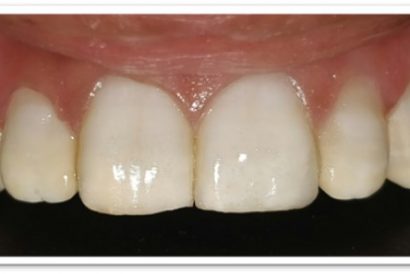

Before

After